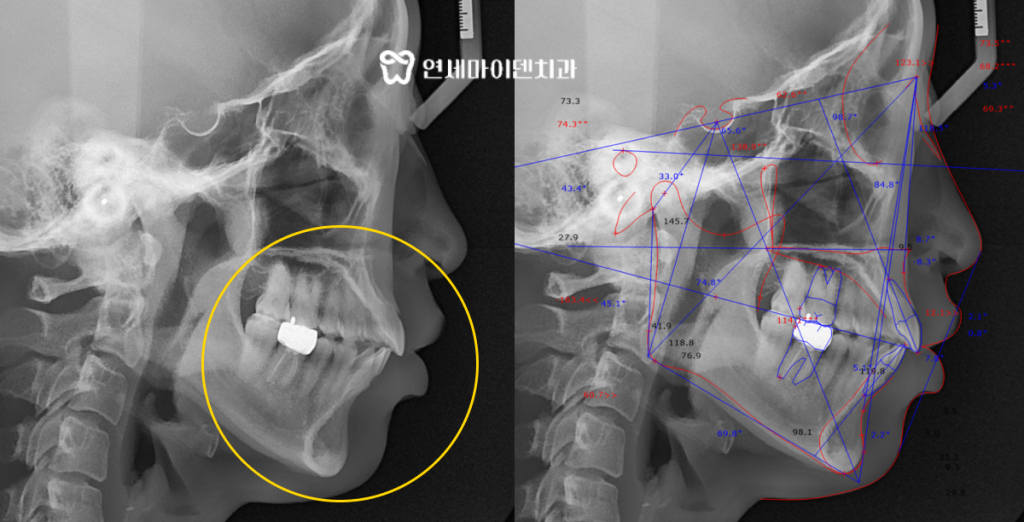

방사선 검사 결과, 위턱과 아래턱의 성장 차이로 인해

골격성 2급 부정교합이 확인되었으며,

특히 앞니의 정상 각도가 105도 내외인 반면

환자분은 100도가 되지 않아서 앞쪽으로 튀어나온 모습이었습니다.

정면 사진에서는 중심선이 우측으로 틀어진 안면 비대칭이 관찰되었으며,

이러한 비정상적인 교합은 턱관절에 부담을 줄 수 있어

신중한 진단과 치료 계획이 필요하다고 판단하였습니다.